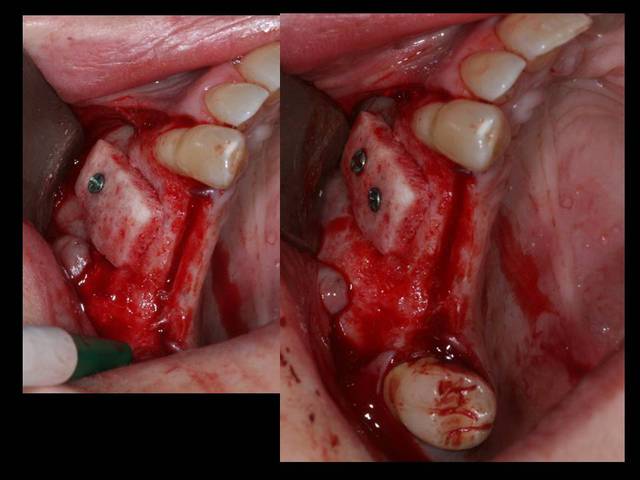

Suite à un post que j'avais mis sur les dégats des gestes iatrogènes dans notre art...

http://www.eugenol.com/sujets/394749-devoir-de-confraternite?page=5

Je poste aujourd'hui la reconstruction.

Je ne sais pas si la résorption est GARANTIE ;+)) mais c'est pour la beauté du geste de toutes les façons.